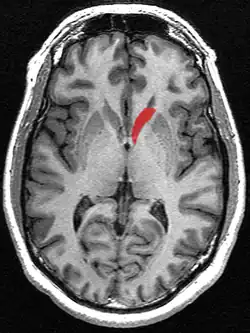

This is a transverse view of the caudate nucleus from a structural MR image.

Transverse view of the caudate nucleus from a structural MR image